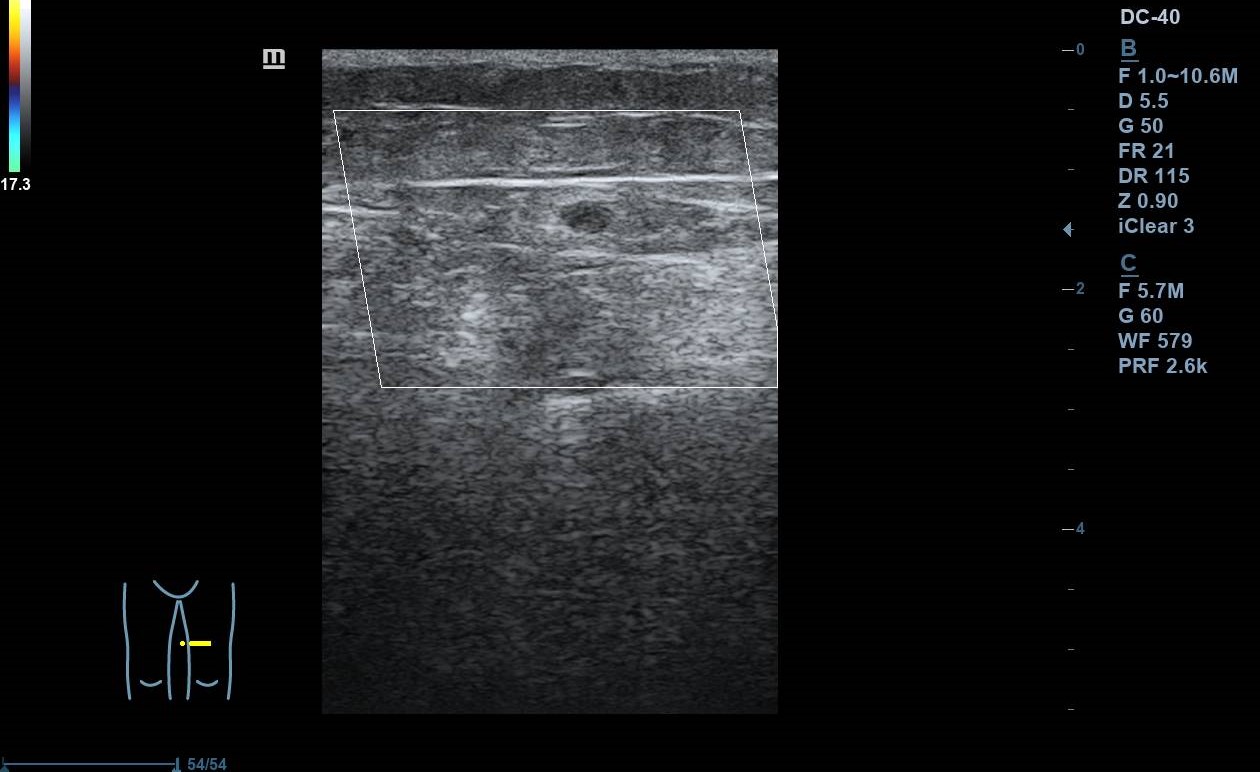

Se realiza ecografía Doppler en el Centro de Salud: se exploran con sonda lineal ambos MMII a nivel inguinal y poplíteo, constatando colapsabilidad, presencia de flujo y ausencia de material ecogénico a nivel de vena femoral común y poplítea. Colocando sonda en el punto doloroso observamos vena safena interna no colapsable. Nos desplazamos superiormente, siguiéndola hasta la unión safenofemoral, sin observar colapsabilidad durante el trayecto.

Juicio clínico: TVS en vena safena interna de al menos 5 cm con afectación próxima a cayado.

Un mes después se repite ecografía en el centro de salud observándose mejoría de la TVS.